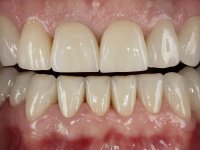

Paciente do sexo masculino, com 42 anos de idade, não fumador. Apresentava uma reabilitação metalo -cerâmica feita há mais de 10 anos com exposições radiculares e infiltrações. No maxilar superior apresentava uma coroa no 1.1,uma ponte de dois elementos no 2.1 e 2.2.e uma ponte de 4 elementos nos dentes 2.4,2.5,2.6 e 2.7 com o 2.6 como pôntico. Os dentes 1.6/1.5/1.4/1.3/1.2/1.1/2.1/2.2/2.3/2.4/2.5 e 2.7 apresentam tratamento endodôntico radical com o 2.4/2.5 e 2.7 a necessitarem de ser refeitos. No maxilar inferior apresentava uma ponte metalo-cerâmica de 4 elementos nos 4 incisivos e uma ponte de 3 elementos (3.3 e 3.4) com um dente supranumerário como pôntico. Os dentes 4.6/4.5 e 4.2 apresentavam tratamento endodôntico com o 4.2 a necessitar de ser refeito. Os dentes 4.3 e 4.4 apresentavam extensas cáries linguais com algum comprometimento mesial. As peças protéticas apresentavam-se infiltradas com exposição radicular associada. Apresentava uma D.V.O. diminuída e uma mordida cruzada lado direito. O paciente tinha uma satisfatória saúde periodontal e uma boa higiene oral.

Foi proposto ao paciente fazer uma reabilitação total com infraestruturas em zircónia revestidas a cerâmica. No maxilar superior, seriam realizadas 6 coroas (1.3/1.2/1.1/2.1/2.2/2.3), uma ponte de 3 elementos (1.4/1.5/1.6) e uma ponte de 4 elementos (2.4/2.5/2.6 e 2.7). No maxilar inferior, foram propostas 7 coroas (4.3/4.2/4.1/3.1/3.2/3.5 /3.6) e duas pontes (4.4//4.5/4.6) e (3.3/3.4#/3.4).O objetivo seria subir a D.V.O., descruzar a mordida do lado direito, eliminar as infiltrações e as exposições radiculares e reabilitar o paciente com estruturas protéticas com aspeto mais natural.

A primeira acção terapêutica foi tentar melhorar o tratamento endodôntico dos dentes (2.4/2.5/4.2)). A sua manutenção em boca seria condicionada pelo sucesso desta intervenção. Seguidamente foram feitas impressões em alginato e registo inter-maxilar em silicone para confeção em laboratório de uma ponte provisória em acrílico com reforço. O objetivo desta ponte provisória seria ensaiar o aumento da D.V.O. e descruzar a mordida do lado direito. Foi utilizado um monobloco de 13 dentes com o dente 2.6 com o pôntico. As coroas e as pontes foram removidas e os remanescentes coronários foram repreparados. A ponte provisória foi rebasada primeiramente com acrílico auto-polimerizável e de seguida com resina composta. Após 2 semanas de permanência em boca, foram feitas as impressões para confeção da ponte provisória inferior também realizada em laboratório. Especial cuidado foi colocado na remoção das coroas antigas, sendo feito primeiramente um corte axial que permitiu que fossem removidas de uma forma menos traumática. A temporização foi feita durante 8 semanas, permitindo que os tecidos gengivais estabilizassem posicionalmente. As impressões definitivas foram realizadas após afastamento gengival utilizando a técnica do fio único impregnado. Foi utilizada a técnica de dupla mistura com dupla viscosidade (putty soft e light).Simultaneamente foi realizada a recolha das relações inter-maxilares e o registo com arco facial. Foram confecçionados os modelos de trabalho e feita a sua correta montagem em articulador semi-ajustável. Em seguida foram feitas infra estruturas em zircónia que posteriormente foram revestidas por cerâmica. A prova de “biscoito” foi realizada em boca para avaliação estética e funcional sendo também avaliado o seu assentamento e ajuste. A reabilitação definitiva foi cimentada em boca utilizando um cimento de ionómero de vidro reforçado por resina.